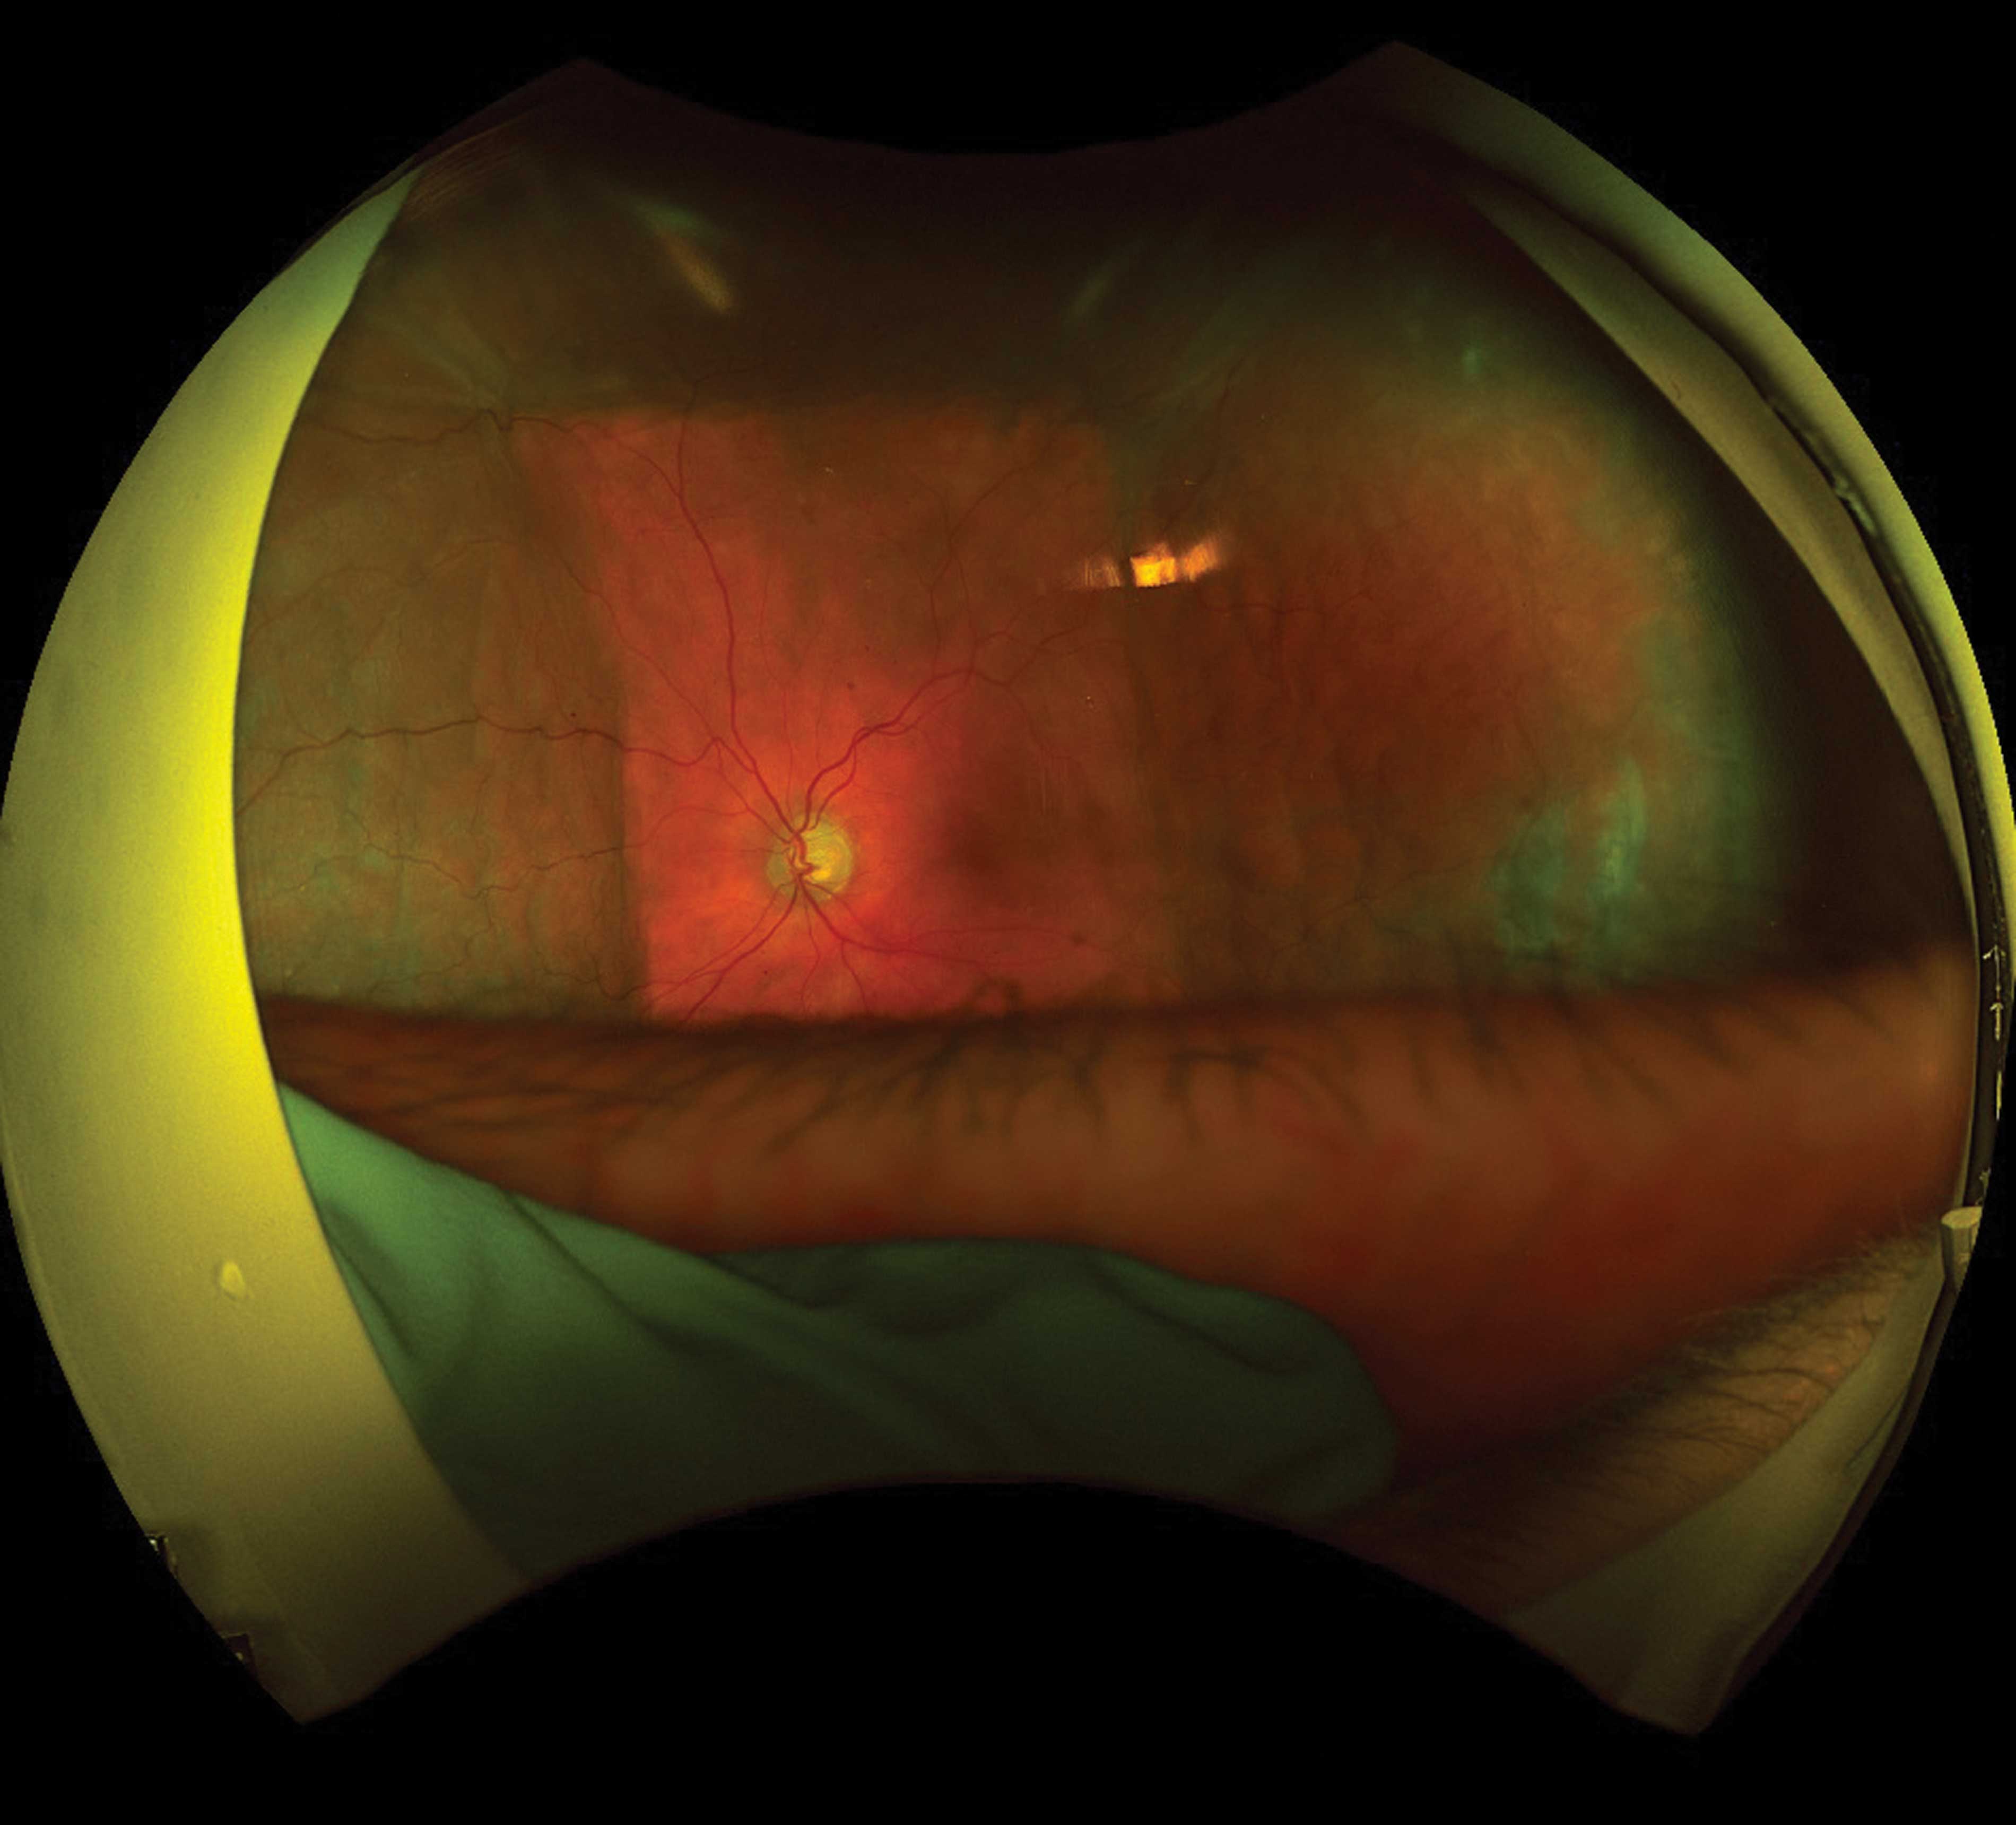

Ultra-widefield imaging in glaucoma: Documenting hypotony-related choroidal effusions after microshunt surgery

Ultra-widefield (UWF) imaging provides extended visualisation of the posterior segment beyond the traditional 30–50° field of view. It captures a broad view of the posterior pole and periphery in a single, quick, non-mydriatic acquisition. While its role in diabetic retinopathy...